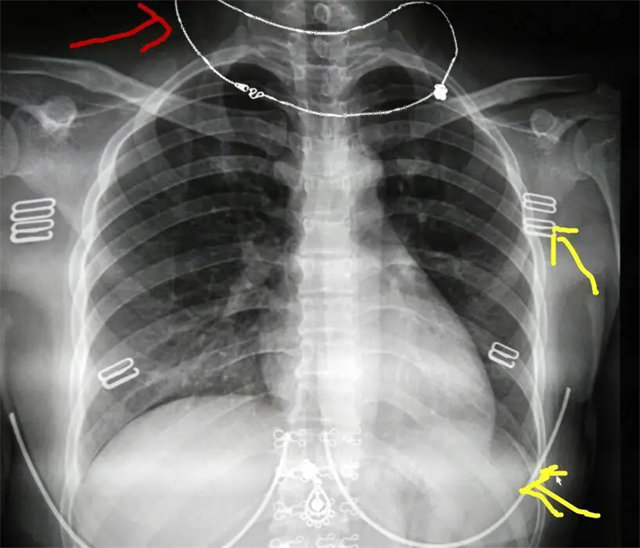

缺陷:兩肩胛骨未拉開肺野之外,吸氣不完全,且存在金屬飾品遮擋。

解決:去除金屬飾品及內(nèi)衣后重新按標(biāo)準(zhǔn)體位攝片即可。